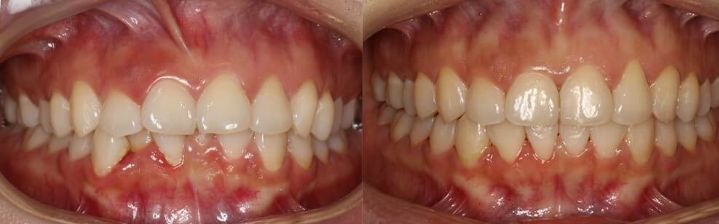

很多人认为,我牙齿很整齐,我没有龅牙没有*牙虎**,我就不需要矫正了。那现在看看,你的咬合是否有问题。图中这个妹砸就是这样,拍摄前她还说,自己的牙没有问题。

当她咬上牙齿,就能发现问题了。这种咬合是典型的深覆合,上牙盖住下牙超过了 1/3 。就像这个女生矫正前微笑时看上去没什么大问题,但是仔细看她的口内情况,就会发现她有明显的深覆合。

矫正前 VS 矫正后经过一年多的矫正时间,女生牙齿排齐,深覆合明显的改善,也不再因为牙齿不美观,而不敢开怀大笑。

矫正前 VS 矫正后而且深覆合,不止美观有问题,还会影响口腔健康。导致不正常的咬合关系,大多数人还会出现磨牙的症状,影响我们的口腔健康。长期还会造成上下颌前牙创伤,会影响上牙前牙的使用寿命,重要的是对关节很不好哦!